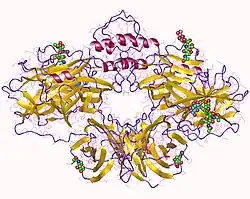

DBH is a 290 kDa copper-containing oxygenase consisting of four identical subunits, and its activity requires ascorbate as a cofactor.[5]

Structure

It was difficult to obtain a stable crystal of dopamine beta-hydroxylase. Hence an homology model based on the primary sequence and comparison to PHM is available.[31]

However, a crystal structure was also put forward in 2016.[32]